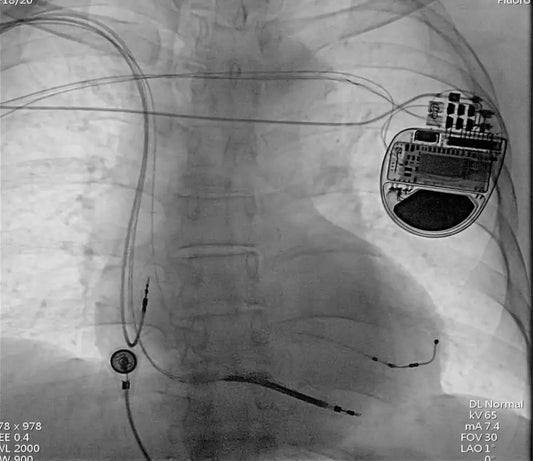

Revolutionary Heart Failure Treatment: CRT-D Implantation for Complex Cardiac Patient at the Fuwai Hospital

A multidisciplinary team at Fuwai Hospital successfully performed a complex 15-hour procedure to implant a Cardiac Resynchronization Therapy Defibrillator (CRT-D) in a patient with advanced heart failure, expanding the possibilities...